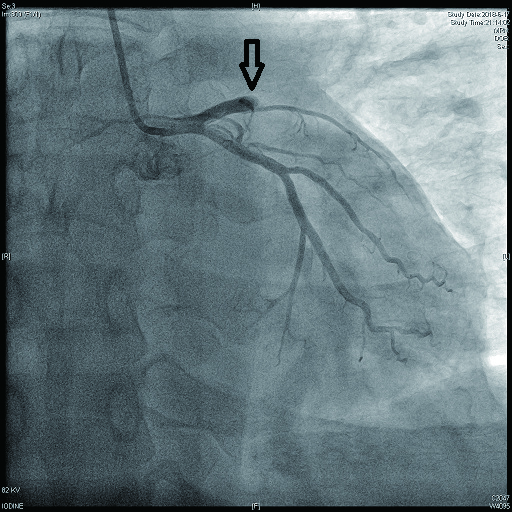

2 结果 本研究收集7例De winter综合征患者,6例进行了急诊冠脉造影,胸痛至球囊扩张平均时间为3.3 h,1例进行择期冠脉造影。其中,3例为前降支近段严重病变,1例为第一对角支闭塞,3例为前降支中段闭塞,2例合并多支血管病变,5例为单支血管病变,均行前降支支架植入术(表 4)。1周内行心脏彩超检查,4例出现室壁运动减弱,2例EF值小于50%,2例心脏形态结构未见异常,1例患者术后第2天因个人原因自动出院,未完善心脏彩超(表 5)。观察7例患者住院期间心电图演变情况,其中有3例在PCI术后出现前壁导联ST段抬高,4例未出现ST段抬高(表 5)。病例1住院期间出现室性心动过速,病例7患在急诊科就诊时发生呼吸心搏骤停,经抢救后送导管室行急诊冠脉造影。另外,所有患者经药物及介入治疗后,均症状缓解出院,院外长期服用阿司匹林100 mg/d+替格瑞洛90 mg/12 h+阿托伐他汀40 mg/瑞舒伐他汀20 mg等药物,出院1个月后电话随访,7例患者均无胸痛、气促发作及再住院,无死亡病例。

表 4 7例患者冠脉造影及介入治疗情况

| 编号 |

是否急诊冠脉造影 |

冠脉造影结果 |

介入治疗情况 |

| 病变血管支数 |

罪犯血管 |

罪犯血管狭窄程度 |

罪犯血管TIMI血流 |

| 病例1 |

是 |

1 |

LAD近段(图 9) |

75%~90% |

2级 |

LAD近段植入支架1枚 |

| 病例2 |

是 |

3(图 6~8) |

LAD近段 |

次全闭塞 |

2级 |

LAD近段植入支架1枚 |

| 注:LAD为左冠状动脉前降支; TIMI为心肌梗死溶栓治疗 |

表 5 7例患者的心电图演变及心脏彩超结果

| 编号 |

心电图是否演变为ST段抬高 |

心脏彩超 |

| 病例1 |

是(图 3~5) |

左心扩大,左室前间壁、前侧壁及心尖部运动减弱,EF 35% |

否(图 1~2) |

心脏形态结构未见异常,EF 56% |